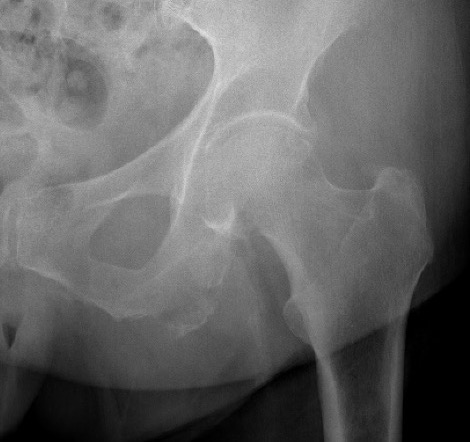

ASIS Avulsion

Attachments

Sartorius & Tensor fascia lata

Imaging

ASIS displaced 1ASIS displaced 2